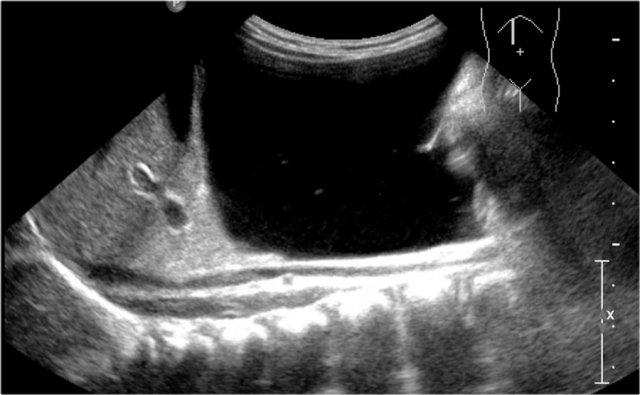

Đây là trường hợp một bé gái được phát hiện nang từ trước sinh.

Siêu âm cho thấy nang có cấu trúc nhiều lớp và hai buồng trứng bình thường.

Trong phẫu thuật, một đoạn hồi tràng đôi đã được cắt bỏ.